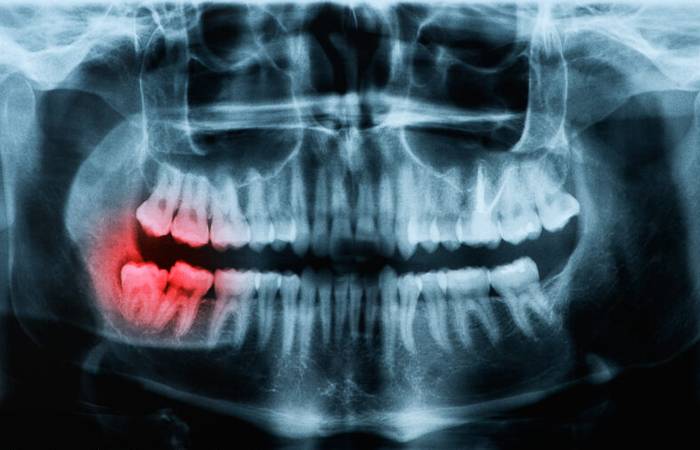

Oral surgery includes the removal of impacted and buried teeth or roots that your own general dentist may not be able to treat.

Leaving bits of teeth and roots in can give rise to infections causing pain and swelling. Many patients put off these treatments for tooth extractions in Liverpool as they worry they may be long or uncomfortable to have done.

Yes we remove impacted teeth.